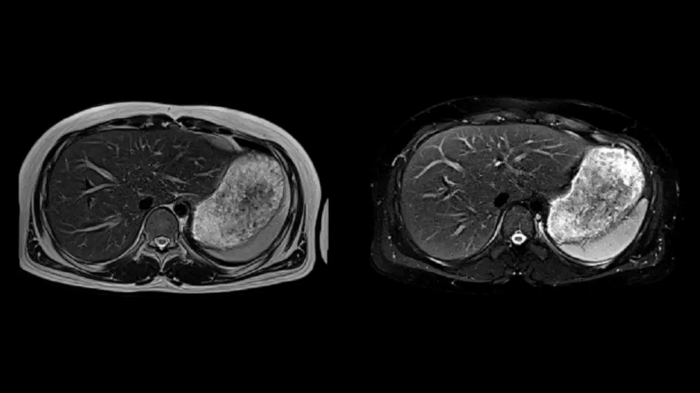

Abdomen

T2 BLADE

T2 motion insensitive abdominal imaging with BLADE results in outstanding outcomes, regardless of the orientation or if fat saturation is needed.

MAC-ID: 7aaaa0165. Image Credit: Siemens Healthineers